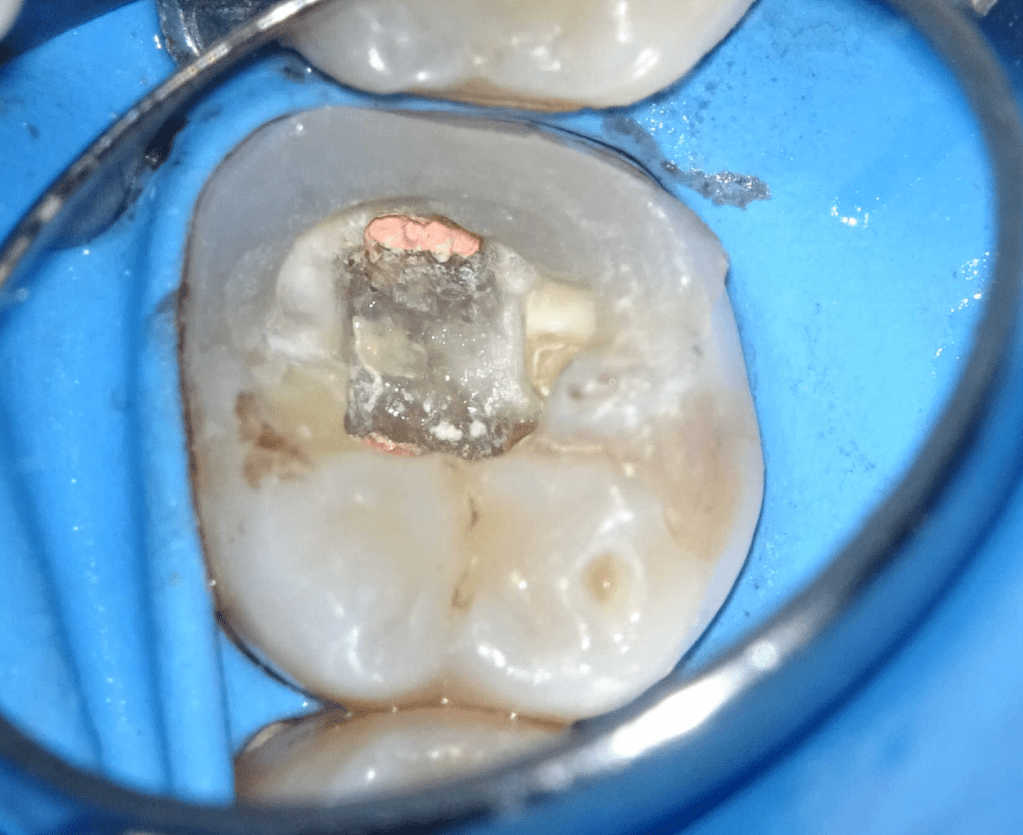

Fisura, remoción amalgama para explorar